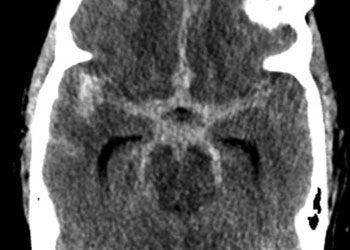

Spine:

Central Cord Syndrome

Author: Yusef Imani M.D., F.A.A.N.S., Read More!